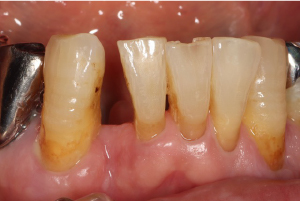

症例

メリーランドブリッジ

治療前

治療後

歯周病により下の前歯を抜歯しました。左隣りの表面を薄く削り、セラミックブリッジを接着しました。右隣りの犬歯とは重なって見えますが、自然に見える仕上がりです。